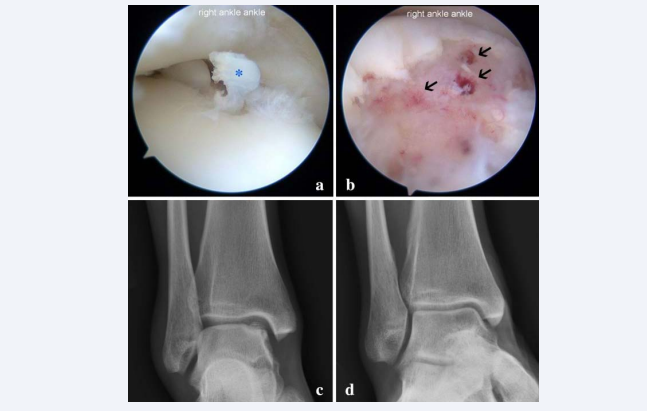

Figure 5 Application of ankle arthroscopy.  (a) Osteochondral lesion of talus with full-thickness cartilage flap (asterisk).  (b) Debridement and micro-fracture stimulates subchondral bleeding and development of a fibrin clot (arrows).  (c) Pre-operative XR showed significant talar dome chondral defect with subcondral sclerosis.  (d) Satisfactory chondral remodelling occurred in 4 months post-operatively

Figure 5 Application of ankle arthroscopy.

(a) Osteochondral lesion of talus with full-thickness cartilage flap (asterisk).

(b) Debridement and micro-fracture stimulates subchondral bleeding and development of a fibrin clot (arrows).

(c) Pre-operative XR showed significant talar dome chondral defect with subcondral sclerosis.

(d) Satisfactory chondral remodelling occurred in 4 months post-operatively